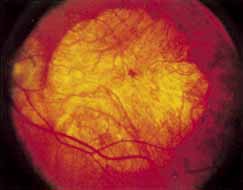

During the early stage of the dystrophy, when patients demonstrate a slight-to-moderate decrease in visual acuity and minimal color defects, there are minor or no visible fundus abnormalities. At most, the foveal reflex may be absent and there may be some increased granularity of the retinal pigment epithelium in the macula. Later, there is a decrease of visual acuity to the 20/400 range, oval atrophy of the macular retinal pigment epithelium (“beaten bronze” atrophy), and associated choroidal atrophy (Fig. 3). A characteristic bull's-eye maculopathy, similar to that seen in patients with chloroquine retinopathy, may also be seen.90 Photophobia, occasional nyctalopia, incomplete-to-complete color defects, and a central scotoma are often present. The symmetry of the process in both eyes is remarkable.